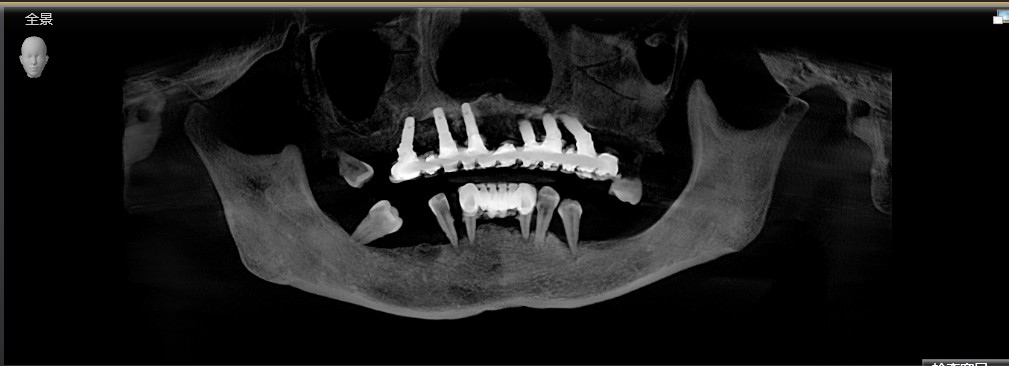

这是一位今天种植牙复诊患者的牙齿的,早期因为牙齿缺失和牙齿松动,严重影响美观,更影响了她的饮食,15年前我为她种了上半口,一直用得很好!但下合的牙因重度牙周病引起牙齿松动和脱落,今年我又为她种了下半口;经过采用种植牙的方式,使得她的牙齿重换新生,患者说:“戴上牙以后什么都能吃,体重还重了许多,很庆幸当时选择种牙这个选择”。

术后图片